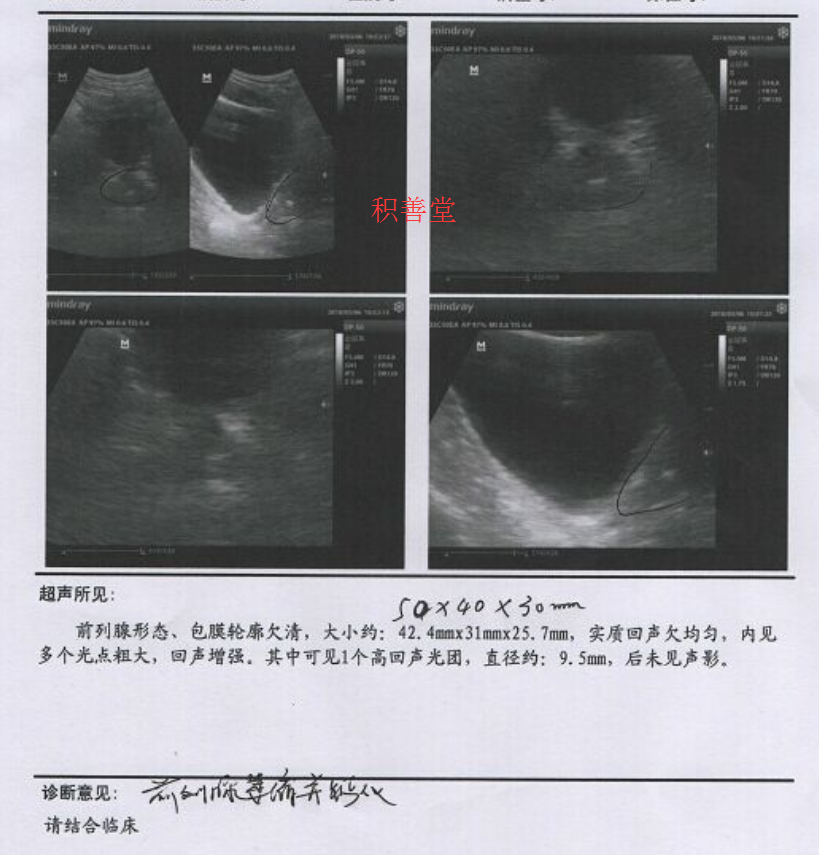

他的B超检查显示:前列腺形态正常,包膜轮廓清晰,大小约:42.4mmx31mmx25.7mm,实质回声欠均匀,内见多个光斑粗大,回声增强。其中可见1个高回声光团,直径约:9.5mm,后未见声影。

傅某已经48岁,这个年龄段的男士前列腺应该出现增大才正常,而他的腺体体积明显没有达到这个年龄段的标准,门诊主任确诊他患的是前列腺萎缩伴钙化。

B超检查显示前列腺形态正常,包膜轮廓清晰,大小约40.2mmx27.6mmx24.8mm,实质回声欠均匀,内见多个光斑粗大,回声增强。其中可见1个高回声光团,直径约:7.8mmx3.9mm,后未见声影